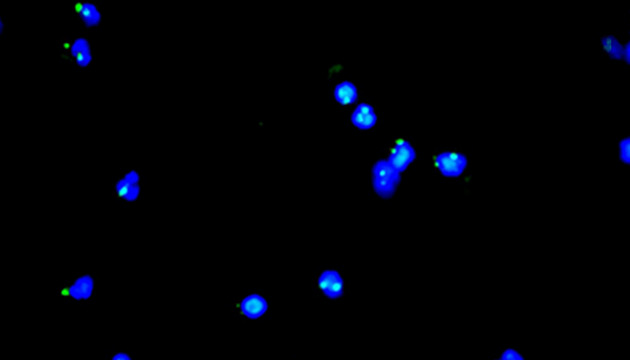

CTC檢測用于上皮腫瘤,如胃腸癌、皮膚癌等。檢測分四步:富集、CD45染白細胞、CK染CTC、DAPI染核。有DAPI、CK熒光且無CD45熒光,大核細胞為CTC;有DAPI、CD45熒光為白細胞。